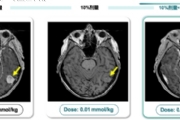

携手全球影像药剂巨头,深透科技AI技术驱动医学影像全方位智能升级